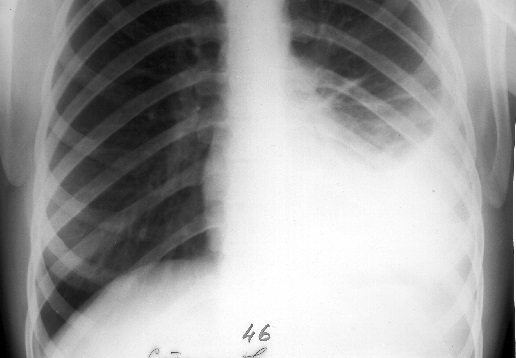

Наряду с клиническими проявлениями экссудативного плеврита при осмотре пациента выявляется асимметрия грудной клетки, выбухание межреберных промежутков на соответствующей половине грудной клетки, отставание пораженной стороны при дыхании. Перкуторный звук над экссудатом притуплен, бронхофония и голосовое дрожание ослаблены, дыхание слабое или не выслушивается. Верхняя граница выпота определяется перкуторно, при рентгенографии легких или при помощи УЗИ плевральной полости.